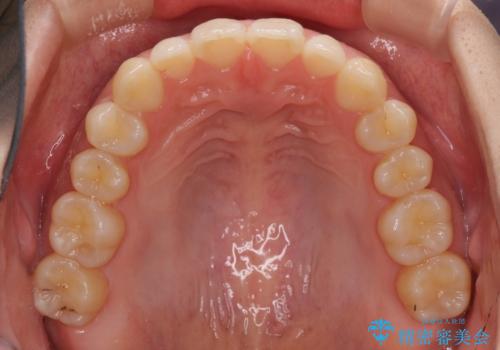

海外勤務中でも矯正治療 インビザラインによる軽度叢生改善

- 前歯のデコボコを気にして来院された患者様です。

治療期間中に海外勤務になる可能性が高いことが分かっていましたが、矯正治療を始めたいとのことでしたので、インビザラインを用いて治療することとしました。

通常であれば半年から10ヶ月程度で終了する歯並びでしたが、海外に長期出張することになったため、1年10ヶ月の期間を要しました。

出張に行かれてしまうと追加のマウスピースを発注できないため、マウスピースの交換頻度を低くし、一時帰国のタイミングに合わせていくことで、スムーズに進めて行くことができました。